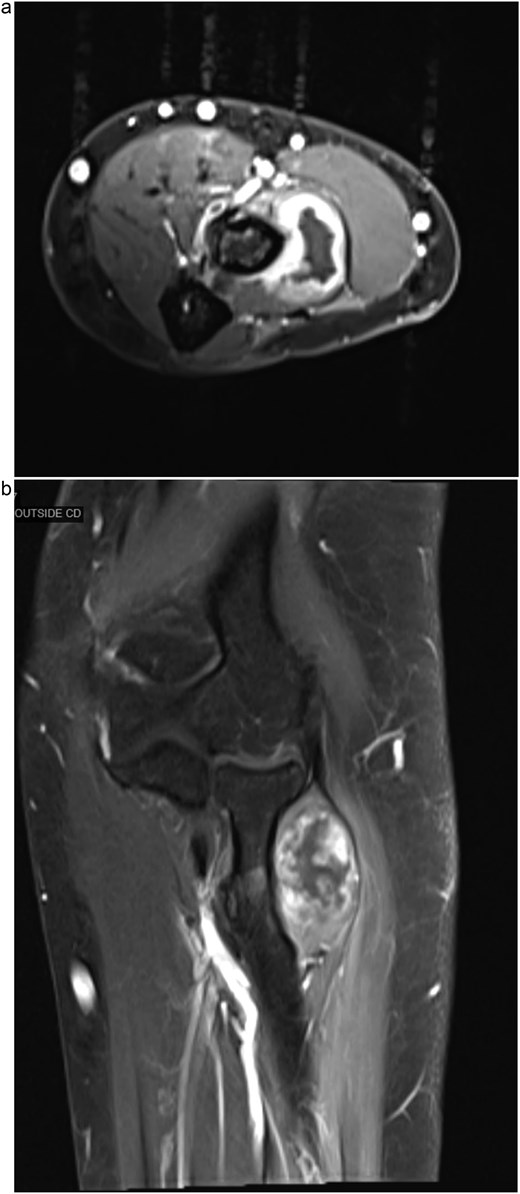

The clinical findings raised concern for a space-occupying lesion causing nerve compression, and further diagnostic workup was initiated with magnetic resonance imaging (MRI), which revealed a well-defined, oval-shaped intramuscular mass located within the supinator muscle, measuring 3.2 × 2.1 × 1.8 cm. The lesion demonstrated homogeneously low-to-intermediate signal intensity on T1-weighted images and markedly high signal intensity on T2-weighted images, consistent with its high mucinous content. Post-contrast images showed mild to moderate peripheral or septal enhancement, with no evidence of infiltration into adjacent structures (Fig. 1).

(a) Axial MRI of the forearm demonstrating a mass within the supinator muscle, associated with compression of the PIN. (b) Coronal MRI of the forearm showing a well-defined intramuscular mass within the supinator muscle, with surrounding edema and displacement of adjacent neurovascular structures.